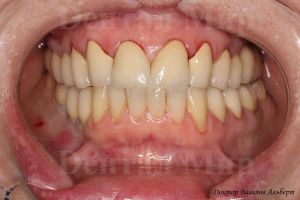

Фотография до и после работы.